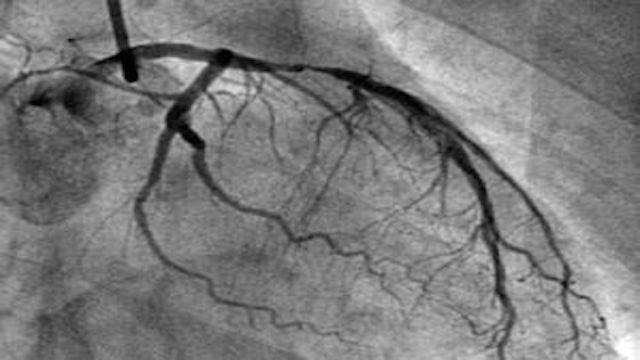

Enfin, il est temps de parler du roi des examens cardio-vasculaires. La coronarographie est bien plus ancienne que moi : depuis 1959, date de la première coronarographie réalisée par le Dr Sones du Centre médical de Cleveland aux États-Unis, l'histoire de la coronarographie remonte à près de 56 ans. Depuis sa création, la coronarographie est devenue l'étalon-or de la maladie coronarienne en raison de ses caractéristiques intuitives et objectives.

La signification de l'indice d'or pour le diagnostic de la maladie coronarienne est un peu comme le testament de l'empereur, qui dit oui ou non. Quels que soient les examens effectués sur les artères coronaires, dès lors qu'une coronarographie a été réalisée, tout dépend des résultats de la coronarographie. La coronarographie consiste à insérer un cathéter épais à cœur de stylo à bille dans l'artère fémorale ou l'artère radiale, à le placer dans l'ouverture de l'artère coronaire et, grâce à l'injection d'un produit de contraste et au développement de l'image, à observer l'alignement, le nombre et la déformation des vaisseaux de l'artère coronaire sous le produit de contraste ; à évaluer l'existence, la gravité et l'étendue des lésions de l'artère coronaire ; à évaluer les changements fonctionnels des artères coronaires, y compris le spasme des artères coronaires et la présence ou l'absence de circulation dans les branches latérales ; en même temps, elle peut également prendre en compte le côté gauche de l'artère coronaire et évaluer les changements fonctionnels des artères coronaires. Évaluation des modifications fonctionnelles des artères coronaires, y compris le spasme des artères coronaires et la circulation des branches latérales ; en même temps, elle peut prendre en compte l'évaluation de la fonction cardiaque gauche. On peut dire que cet examen couvre fondamentalement tous les examens liés au cœur, à l'exception de l'électrophysiologie.

2, la coronarographie : il s'agit d'un examen invasif, par ponction artérielle, le cathéter est introduit dans l'ouverture de l'artère coronaire, l'agent de contraste y est injecté et la situation de remplissage à l'intérieur du vaisseau sanguin et la vitesse du flux sanguin sont observées aux rayons X ; ce type d'examen permet de voir directement la situation à l'intérieur du vaisseau sanguin, c'est donc l'indice d'or pour le diagnostic de la maladie coronarienne, mais l'inconvénient est qu'il s'agit d'un examen invasif ;

- La coronarographie est une technique de pointe en matière de plomberie.Le principe de la coronarographie est similaire à celui de l'angiographie coronaire, mais la coronarographie est un examen invasif au cours duquel un tube est envoyé par une artère de la main ou de la cuisse jusqu'aux artères coronaires du cœur, où un agent de contraste est injecté directement dans les artères coronaires, et la morphologie des artères coronaires est visualisée sur une caméra de film (DSA).Ce test est l'étalon-or pour le diagnostic de la maladie coronarienne, et il est capable de voir non seulement le tronc principal et les grandes branches des artères coronaires, mais aussi certaines des branches plus petites. On dit qu'il s'agit d'un plombier avancé, surtout parce qu'il peut être utilisé non seulement pour diagnostiquer la maladie coronarienne, mais aussi pour délivrer des ballons ou des stents, etc. à travers ce cathéter en vue d'un traitement, ce qui est connu sous le nom de thérapie interventionnelle coronarienne.

coronarographie

La coronarographie reste l'examen de référence pour le diagnostic clinique de la maladie coronarienne, mais elle présente l'inconvénient de nécessiter l'utilisation de produits de contraste et de procédures interventionnelles invasives. Pour évaluer le degré de sténose des artères coronaires, la coronarographie peut évaluer les changements fonctionnels des artères coronaires, y compris le spasme des artères coronaires et la présence ou l'absence de circulation collatérale ; en même temps, elle peut également prendre en compte l'évaluation de la fonction du cœur gauche et ainsi de suite. S'il est confirmé qu'un stent peut être placé dans la zone infarcie pour reconstruire le flux sanguin, un stent doit être implanté directement pour ouvrir le flux sanguin dès que possible, afin de minimiser les dommages myocardiques provoqués par l'infarctus aigu.

Le diagnostic et la classification de la maladie coronarienne sont souvent basés sur une combinaison des caractéristiques des symptômes cliniques, de l'évaluation des facteurs de risque, de l'électrocardiogramme, des tests de laboratoire et de l'imagerie. Cependant.De tous les tests, celui qui peut fournir une preuve directe de la maladie vasculaire est la coronarographie, qui est donc connue comme "l'étalon-or" pour le diagnostic de la maladie coronarienne.。

Pour la plupart des patients soupçonnés d'être atteints d'une maladie coronarienne grave, les médecins recommanderont une coronarographie afin d'évaluer en détail le degré de sténose de l'artère coronaire et, sur cette base, la maladie coronarienne peut être traitée directement par des techniques de pose d'endoprothèses coronariennes.

La coronarographie est actuellement l'examen de référence pour le diagnostic des maladies coronariennes. Le cathéter est inséré dans l'ouverture de l'artère coronaire et une petite quantité de produit de contraste est injectée pour montrer le flux sanguin de l'artère coronaire, pour observer de manière dynamique le flux sanguin de l'artère coronaire et la situation anatomique, pour comprendre la nature, la localisation, l'étendue et le degré des lésions de l'artère coronaire, et pour observer les artères coronaires à la recherche de malformations, de calcifications et de la formation d'une circulation collatérale.

4. la coronarographie : c'est l'"étalon-or" pour le diagnostic de la maladie coronarienne. Elle permet de déterminer si les artères coronaires sont rétrécies ou non, le degré, l'étendue et la localisation du rétrécissement, etc. et d'orienter les mesures à prendre pour le traitement. Parallèlement, la ventriculographie gauche permet d'évaluer la fonction cardiaque.